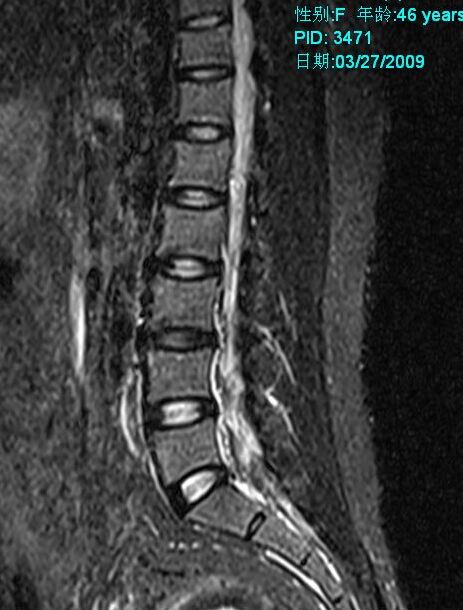

标题: MRI2099:此病人加做压脂像确诊为:终丝脂肪浸润。 [打印本页]

标题: MRI2099:此病人加做压脂像确诊为:终丝脂肪浸润。

此病人加做压脂像:腰1、2椎体平面椎管内条状高信号病灶信号明显降低。以下为压脂像图像: